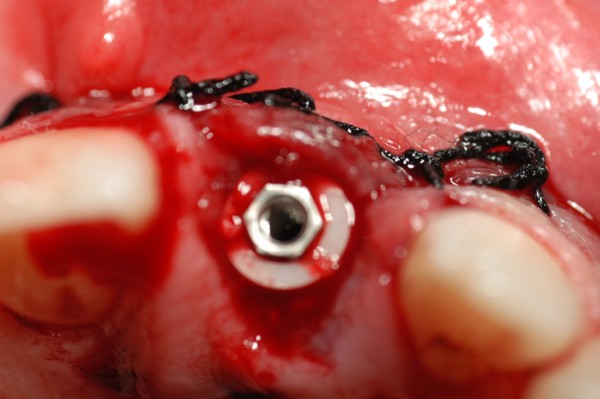

Abstract: Las fuerzas anterógradas traumáticas son en general las causantes de fracturas radiculares en el sector anterior de la boca. Desarrollo: El paciente se presenta a la consulta , con la fractura de una funda de porcelana inyectada en la zona cérvico palatina, solicitando simplemente la reparación en boca para evitar rozamientos linguales. Dicha funda con un perno colado en oro y su correspondiente endodoncia, habían sido realizadas en mi clínica varios años atrás, con un «aparente éxito total». Radiograficamente, se encuentra una fractura radicular cercana al tercio gingival Observada la oclusión de las piezas anteriores, podemos ver que el vínculo ideal de Acoplamiento, no se cumple, habiendo una relación de franco contacto la que ha provocado la fractura. Llevando al paciente a Oclusión en Relación Céntrica, podemos ver el espacio a nivel anterior, correspondiente a la centricidad mandibular. En esa misma posición , es dable percibir una faceta parafuncional mesial del primer premolar superior… …que antagoniza con una faceta parafuncional distal del canino inferior… ..constituyendo un plano inclinado que provoca la antelación mandibular o Discrepancia Horizontal, fracturando la raiz del incisivo central. Extraida la porción coronal de la raiz, pensamos en la realización de un Implante Inmediato, a pesar de la presencia de una fístula dado que se trataba de un central, decisión que obtuvo éxito implantario mas no estético, según veremos luego. Era fundamental conservar lo mas posible las tablas óseas, que de hecho había perdido la porción cervical Realizamos una incisión que conservara las papilas de las piezas adyacentes. Realizamos la exodoncia mediante un instrumento construido «ad hoc» que denomino: Con lo que obtenemos la preservación «ad integrum» de las corticales peridentarias remanentes. Instalamos entonces un implante T.B.R. de 15 mm de largo por 4 mm de diam. con cuello de zirconio de 3,5 mm …quedando tres espiras sin hueso por vestibular, producto de la tabla perdida, Incidimos el periostio a nivel apical del colgajo para obtener mayor paño quirúrgico, y legramos un bolsillo palatino sin incisiones de descarga, para la inserción de la membrana. Suplementamos la carencia ósea vestibular con «BIOSS» …e instalamos una membrana reabsorbible «BIOGUIDE» , que fijamos con el mismo implante, y calzamos por palatino. Suturamos Instalamos nuestra provisional previamente confeccionada, sobre un abuttment de titanio. Y controlamos radiograficamente Pasadas tres semanas del retiro de los puntos, observamos una cicatrización alta que nos muestra el anillo de zirconio del implante. ……………………………………………….. Transcurridos tres meses preparamos una nueva cirugía, dirigida a instalar un injerto autólogo de conectivo en el área del anillo, con un nuevo desplazamiento del colgajo vestibular. Tomamos tejido conectivo del paladar a nivel de los premolares, mediante una incisión mucosa «en libro», y disección del conectivo subyacente. Lo posicionamos en vestibular del anillo de zirconio y lo fijamos mediante sutura Y semanas después nos encontramos con un nuevo fracaso de orden estético. ……………………………………………….. En la actualidad, el caso esta estable , aún con su funda provisional, a la espera de un nuevo intento plástico, mediante Injerto Libre de Encia. ………………………………………………….. ESQUEMA MECÁNICO DEL FENÓMENO …que además de los hechos mostrados en el caso presentado, frecuentemente provocan en el sentido antero posterior los fenómenos de DISPERSIÓN ,en el maxilar superior…y de APIÑAMIENTO en el maxilar inferior. CONCLUSIONES: Además del rigor académico que nos convoca… esta; nuestra casa…nos otorga la confianza que solo da el saber que estamos siempre entre amigos, que cada vez son más. Por tanto es que debo decir: YO fui el responsable de dicha fractura… …porque… …..que hubiera sucedido si hubiera hecho todo el trabajo implantario sin ajustar previamente su oclusión? Seguramente a esta altura del caso…también hubiera fracasado el implante. Siempre decimos que se aprende de los errores más que de los aciertos, y Dr. Carlos A. Acuña Priano

Fig.22(Pie de foto: Membrana)

Fig.24(Pie de foto: funda provisoria en infraoclusión)

Fig.25(Pie de foto: Rx post op.)